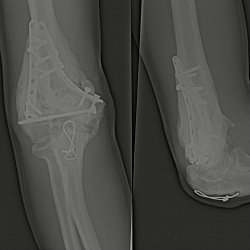

Здравствуйте, подскажите пожалуйста, как описать стопы? Пациент мужчина 40 лет, в анамнезе ревматоидный артрит